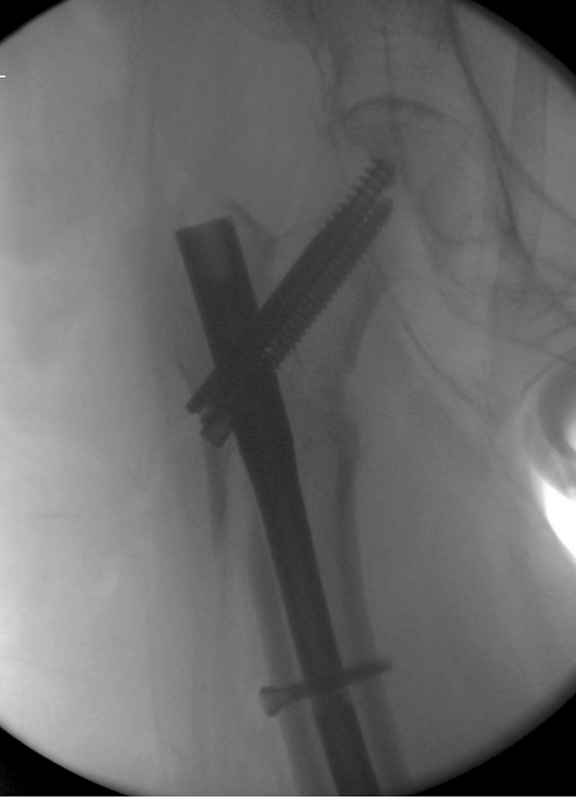

Здесь 83 года, травма в результате падения

судя по картинкам с ЭОПа явно использовались приемы непрямой репозиции под его контролем, а так же интраоперационный ЭОП-контроль положения винтов, без такого контроля операция может ухудшить ситуацию (опять же учтите сроки) т.к. результат буде зависеть в большей степени от искусства хирурга, а не от технологии